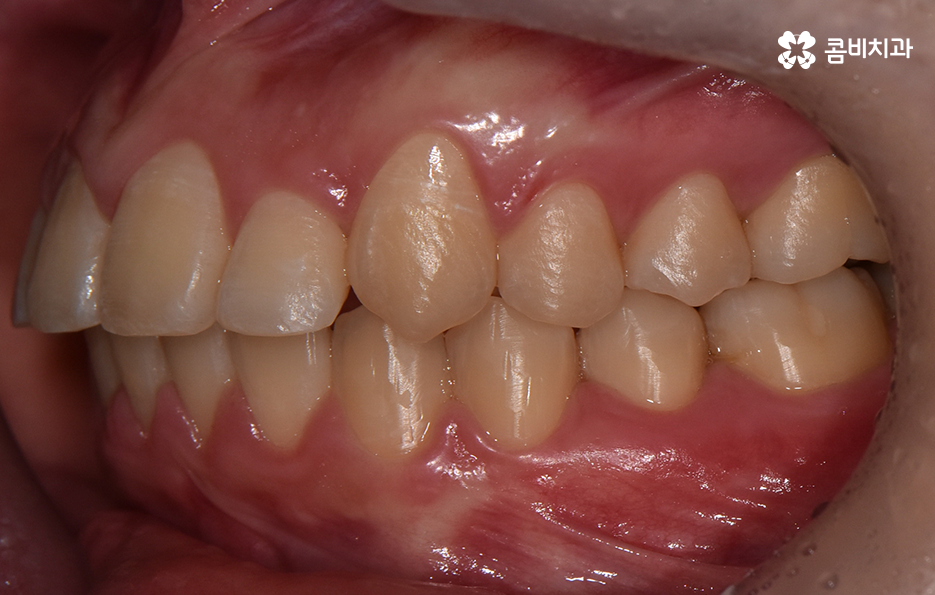

오늘 덧니 비발치 교정 사례로 보시는 환자분의 경우에는 윗니와 아랫니 앞니 부분에 조금씩 덧니가 있는 상태로 덧니를 제외하면 대체적으로 치열 상태는 고른 편이며 덧니 교정 사례 중에서는 돌출입도 함께 개선해야 하는 경우가 많지만 위 환자분의 경우에는 돌출입의 정도가 양호했고 입술라인 역시도 정상 범위에 가까웠기 때문에 발치를 필요로 하지 않았지만 치아의 이동 공간과 보다 자연스러운 입술라인 그리고 얼굴형과의 조화를 고려하여 악궁 확장과 어금니 후방 이동을 적절히 활용하여 교정 치료가 진행되었다고 볼 수 있어요

대부분의 발치 교정의 경우 작은 어금니를 발치하여 치아의 이동 공간을 확보하는 경우가 많다면 덧니 비발치 교정의 경우 발치교정 만큼은 아니더라도 치아를 이동 시킬 공간을 약간이라도 확보해야 하기 때문에 악궁 확장이나 치간삭제를 하는 경우가 있으며 어금니 후방 이동이 필요할 경우에는 사랑니 발치를 해야할 수 있어요